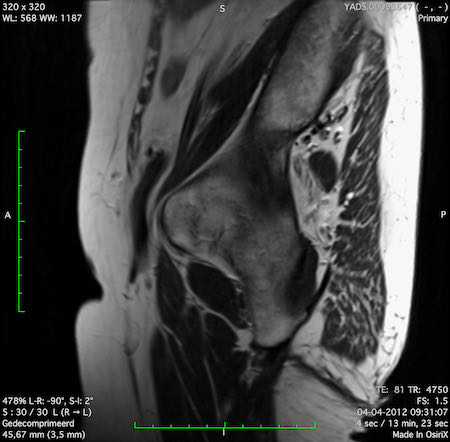

Hình ảnh

Các hình ảnh được cung cấp cho thấy ung thư biểu mô tế bào nhẫn với tình trạng dày lan tỏa thành trực tràng, hình ảnh bia bắn điển hình, và sự xâm lấn mỡ mạc treo trực tràng.